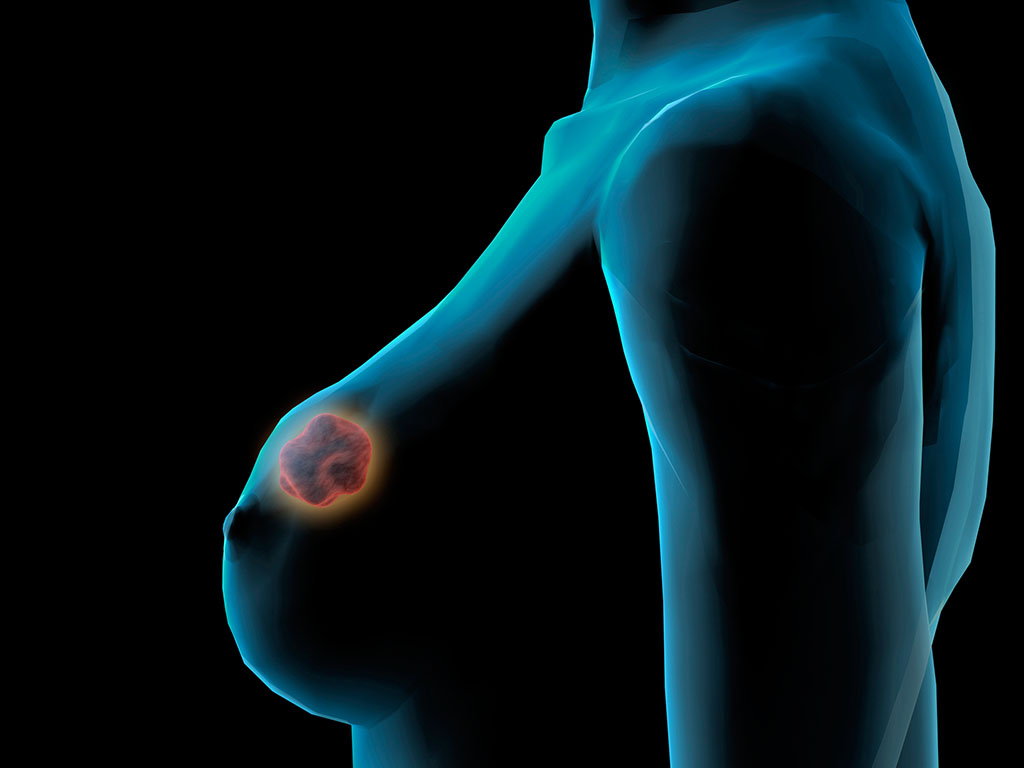

- 去美国看病:晚期乳腺癌实现治愈,不是不可能

- 2016年6月,央视电视台前著名主持人郎永淳妻子乳腺癌肝转抗癌成功已是健康人,引起轩然大波。乳腺癌出现肝转移已经属于癌症晚期,也就是四期,这样的患者竟然被治愈了......

- 去美国看乳腺癌:男性乳腺癌同样不可忽视!

- 在美国,每年有2360名男性诊断为乳腺癌,有430名男性死于乳腺癌。想想中国人口基数,在按比例算算我泱泱大国每年有多少男性患上乳腺癌。并且中国人口性别比例的失调......

- 日本体检:预防男性乳腺癌 贵在“三早”

- 记得前几年在一部电视剧《男人四十要出嫁》中,宋小宝饰演的男主角周六福就是患了乳腺癌。当时此情节一经播出,不少网友表示惊呆了:没想到,男人竟然也会患上乳腺癌!这个......